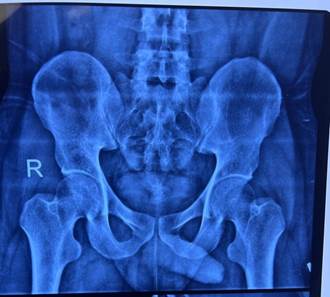

X-Ray pelvis

ruled out any pelvic fracture as depicted in Figure 1. The patient's blood

Figure 1. X-ray pelvis showing no obvious bony

injury.